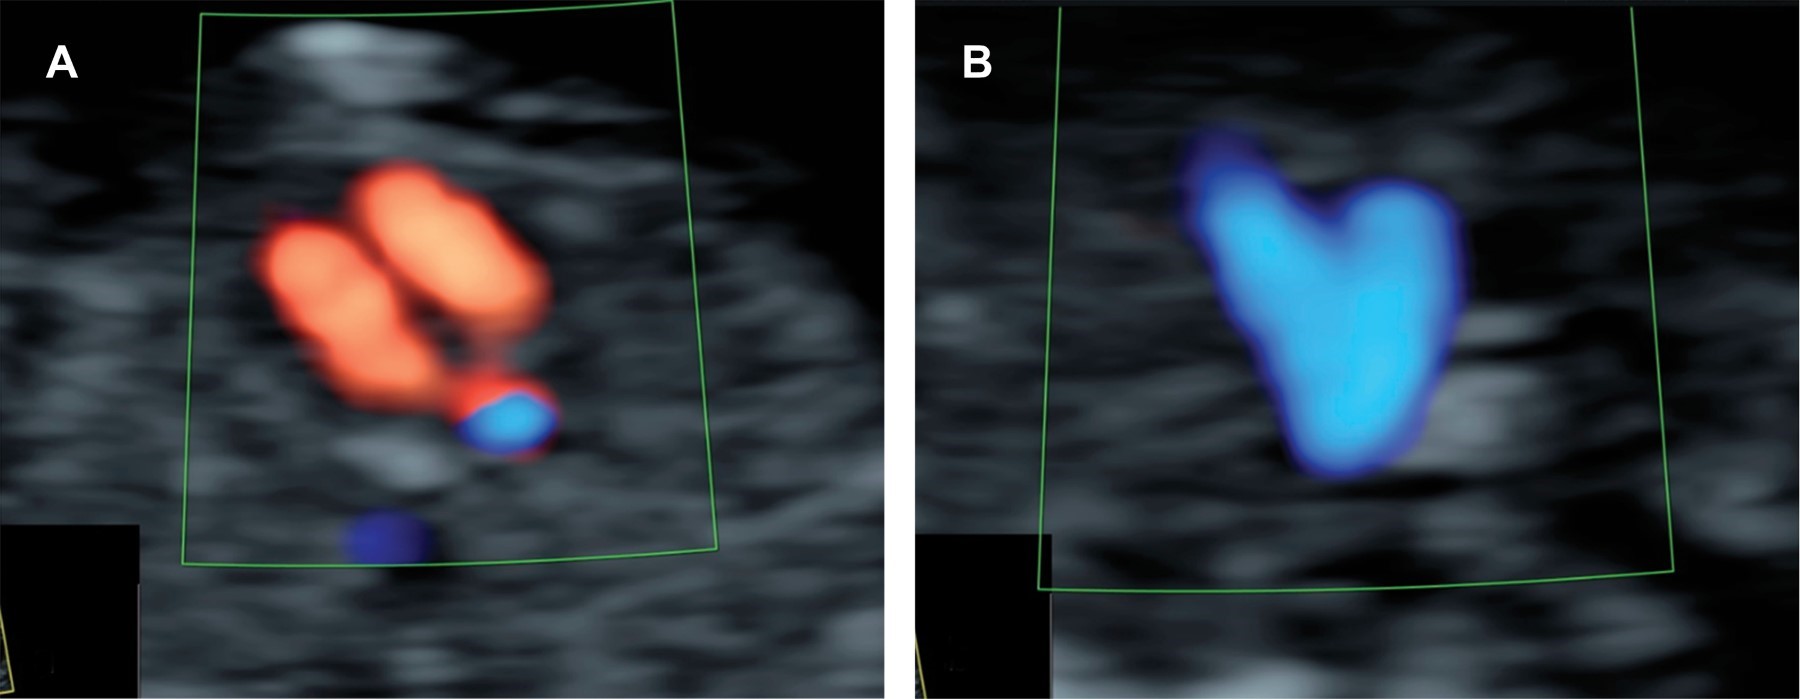

Figure 3